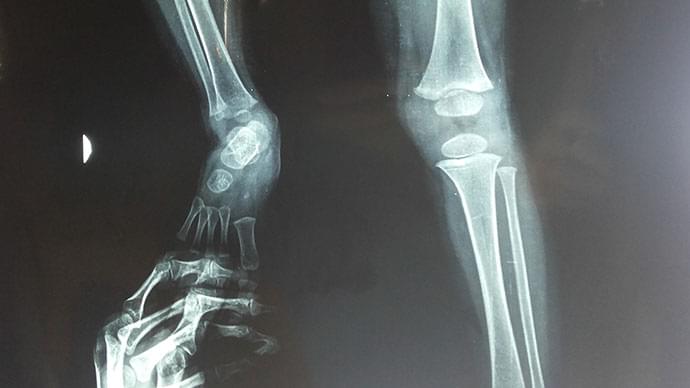

Ortopedia Infantil